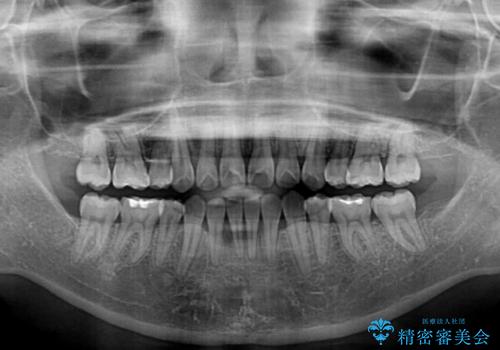

- 口元の突出感と口の閉じにくさを気にして来院された患者様です。

上下左右第一小臼歯4本を抜歯し、ワイヤー装置にて口元を引っ込めるよう矯正治療を行うこととしました。

2年~2年半が治療期間の目安でしたが、順調に治療が進み、1年9か月で満足のいく歯列となりました。